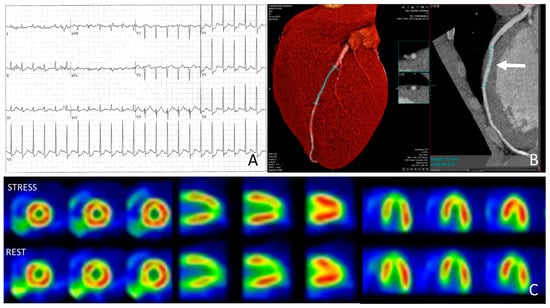

4.3. Athlete with Anomalous Origin of the Coronary Arteries with Interarterial Course